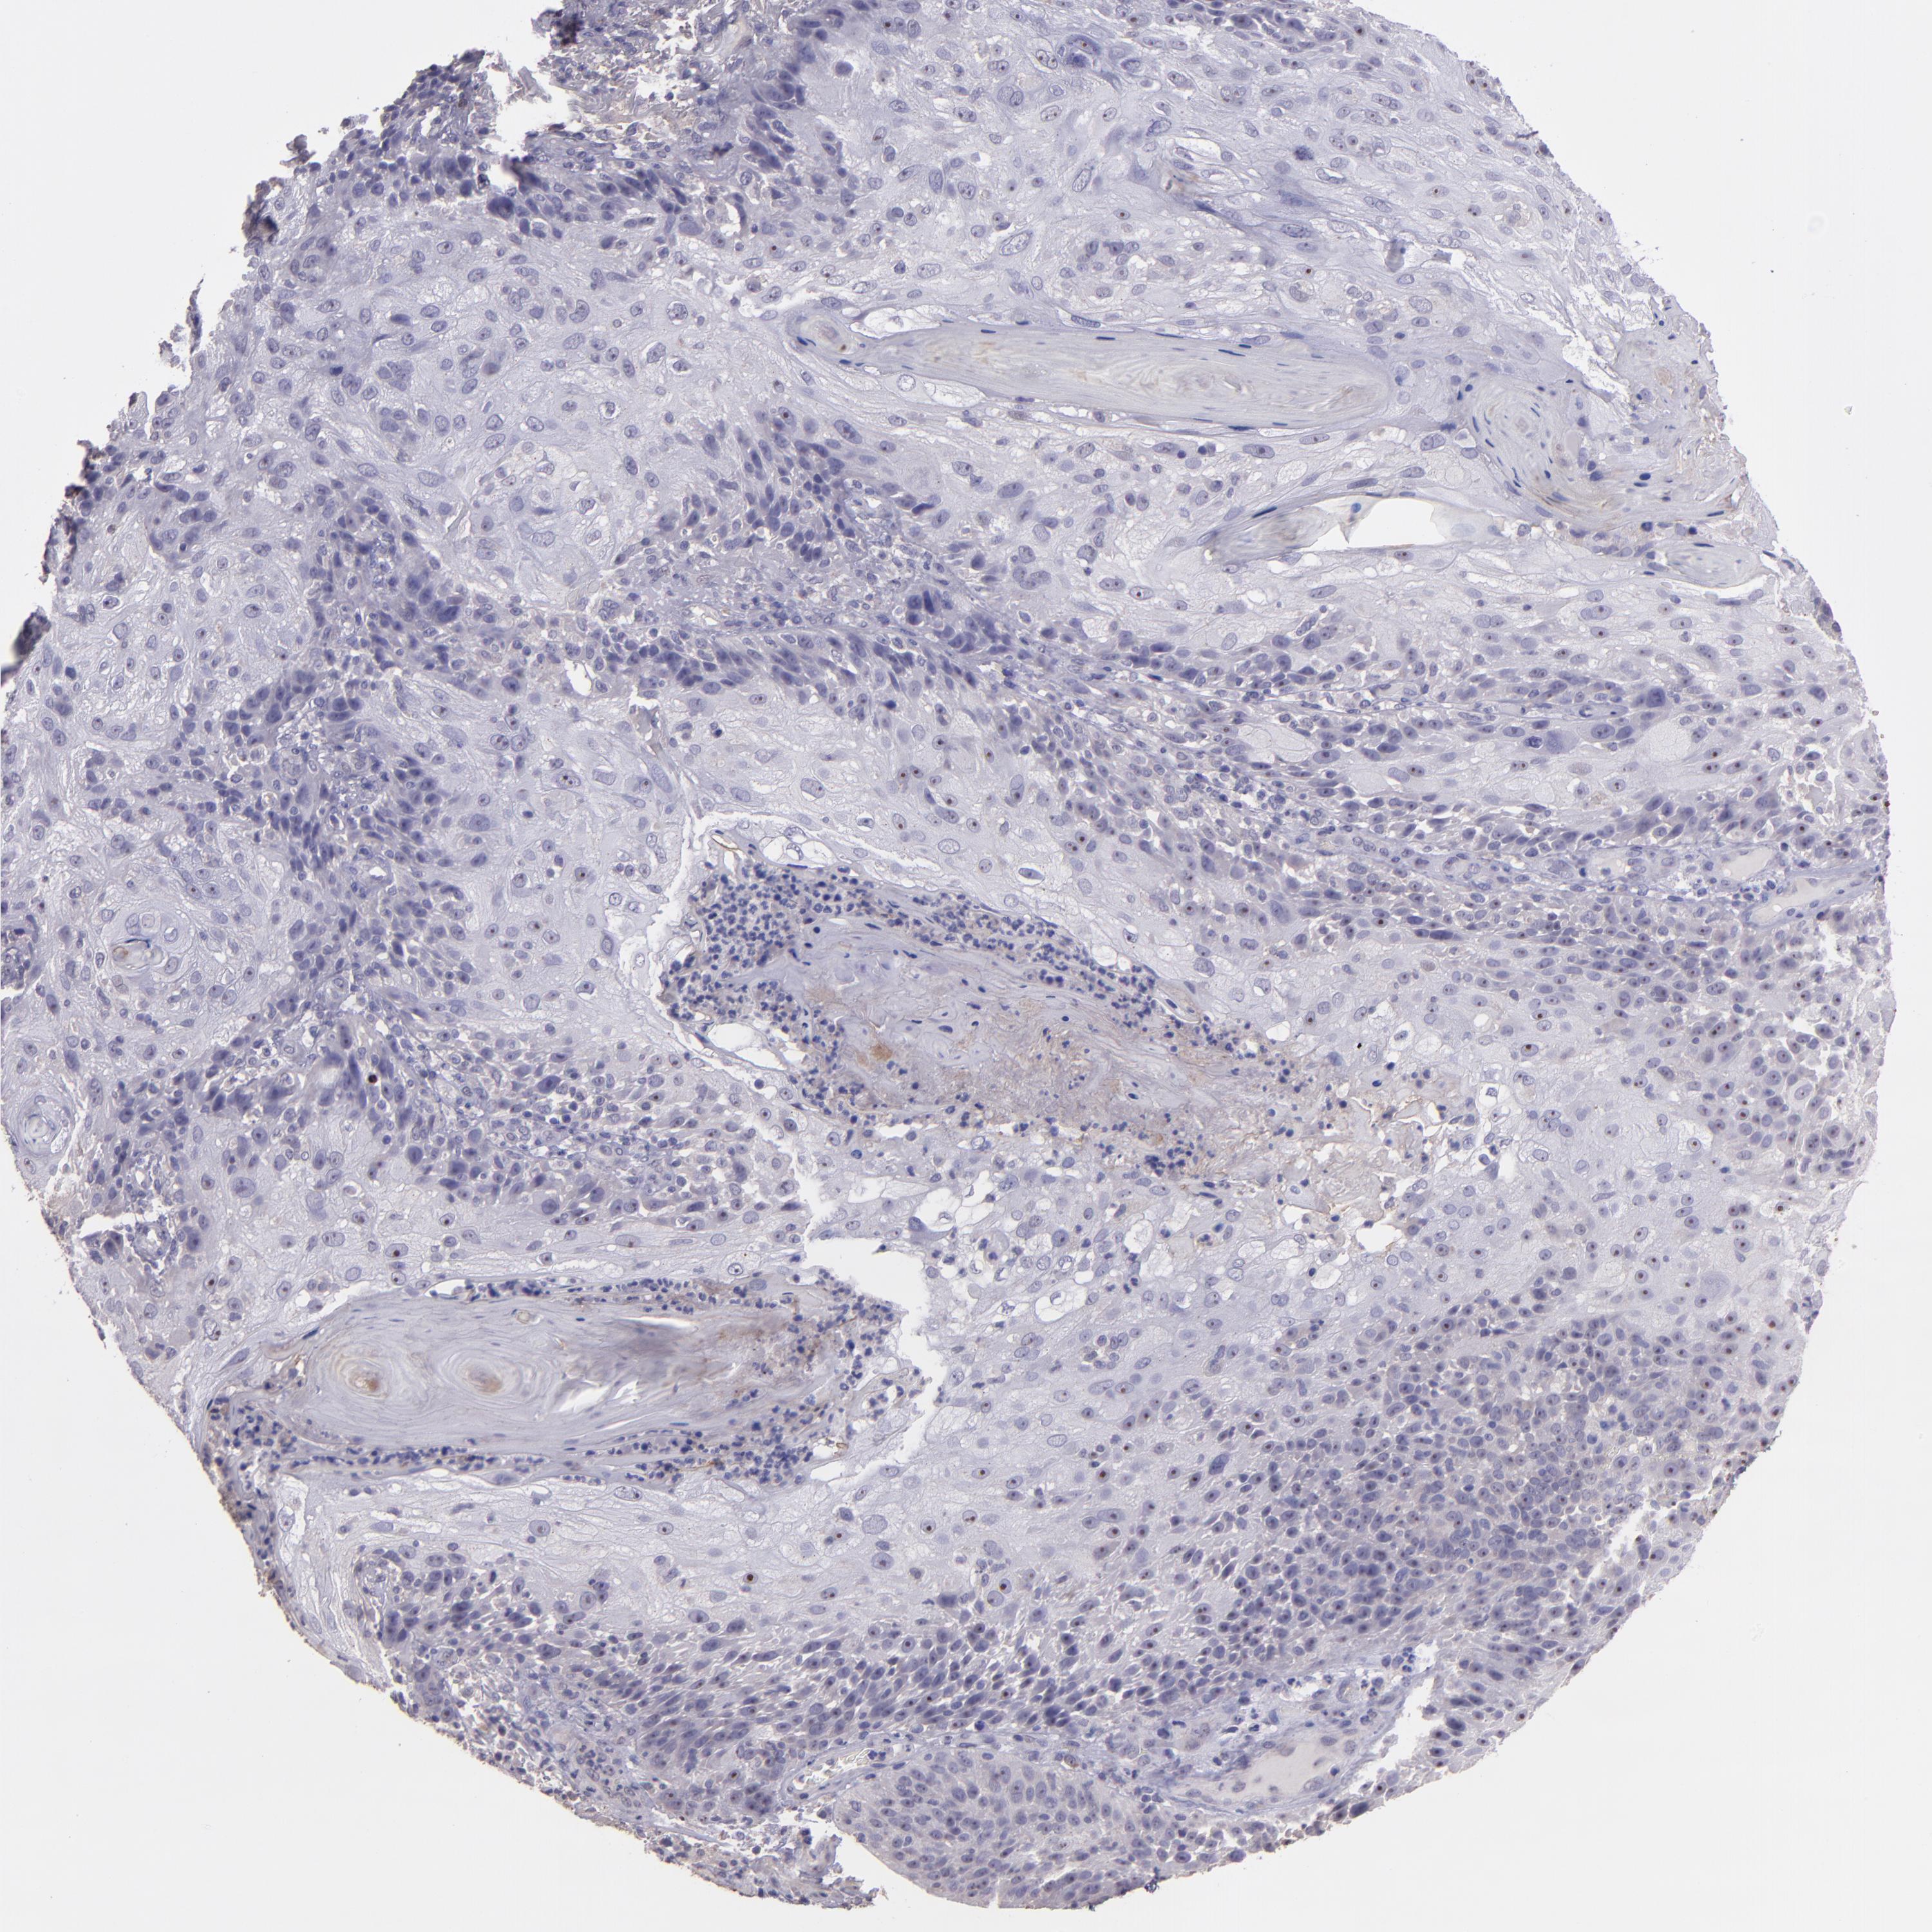

SKIN CANCER - Protein expressioni

A mouse-over function shows sample information and annotation data. Click on an image to view it in a full screen mode. Samples can be filtered based on level of antibody staining by selecting one or several of the following categories: high, medium, low and not detected. The assay and annotation is described here.

Each image is clickable and will lead to virtual microscopy that enables deeper exploration of all samples and also displays staining intensity scores, fraction scores and subcellular localization as well as patient and tissue information for each sample.

Antibody CAB016724

Squamous cell carcinoma, NOS